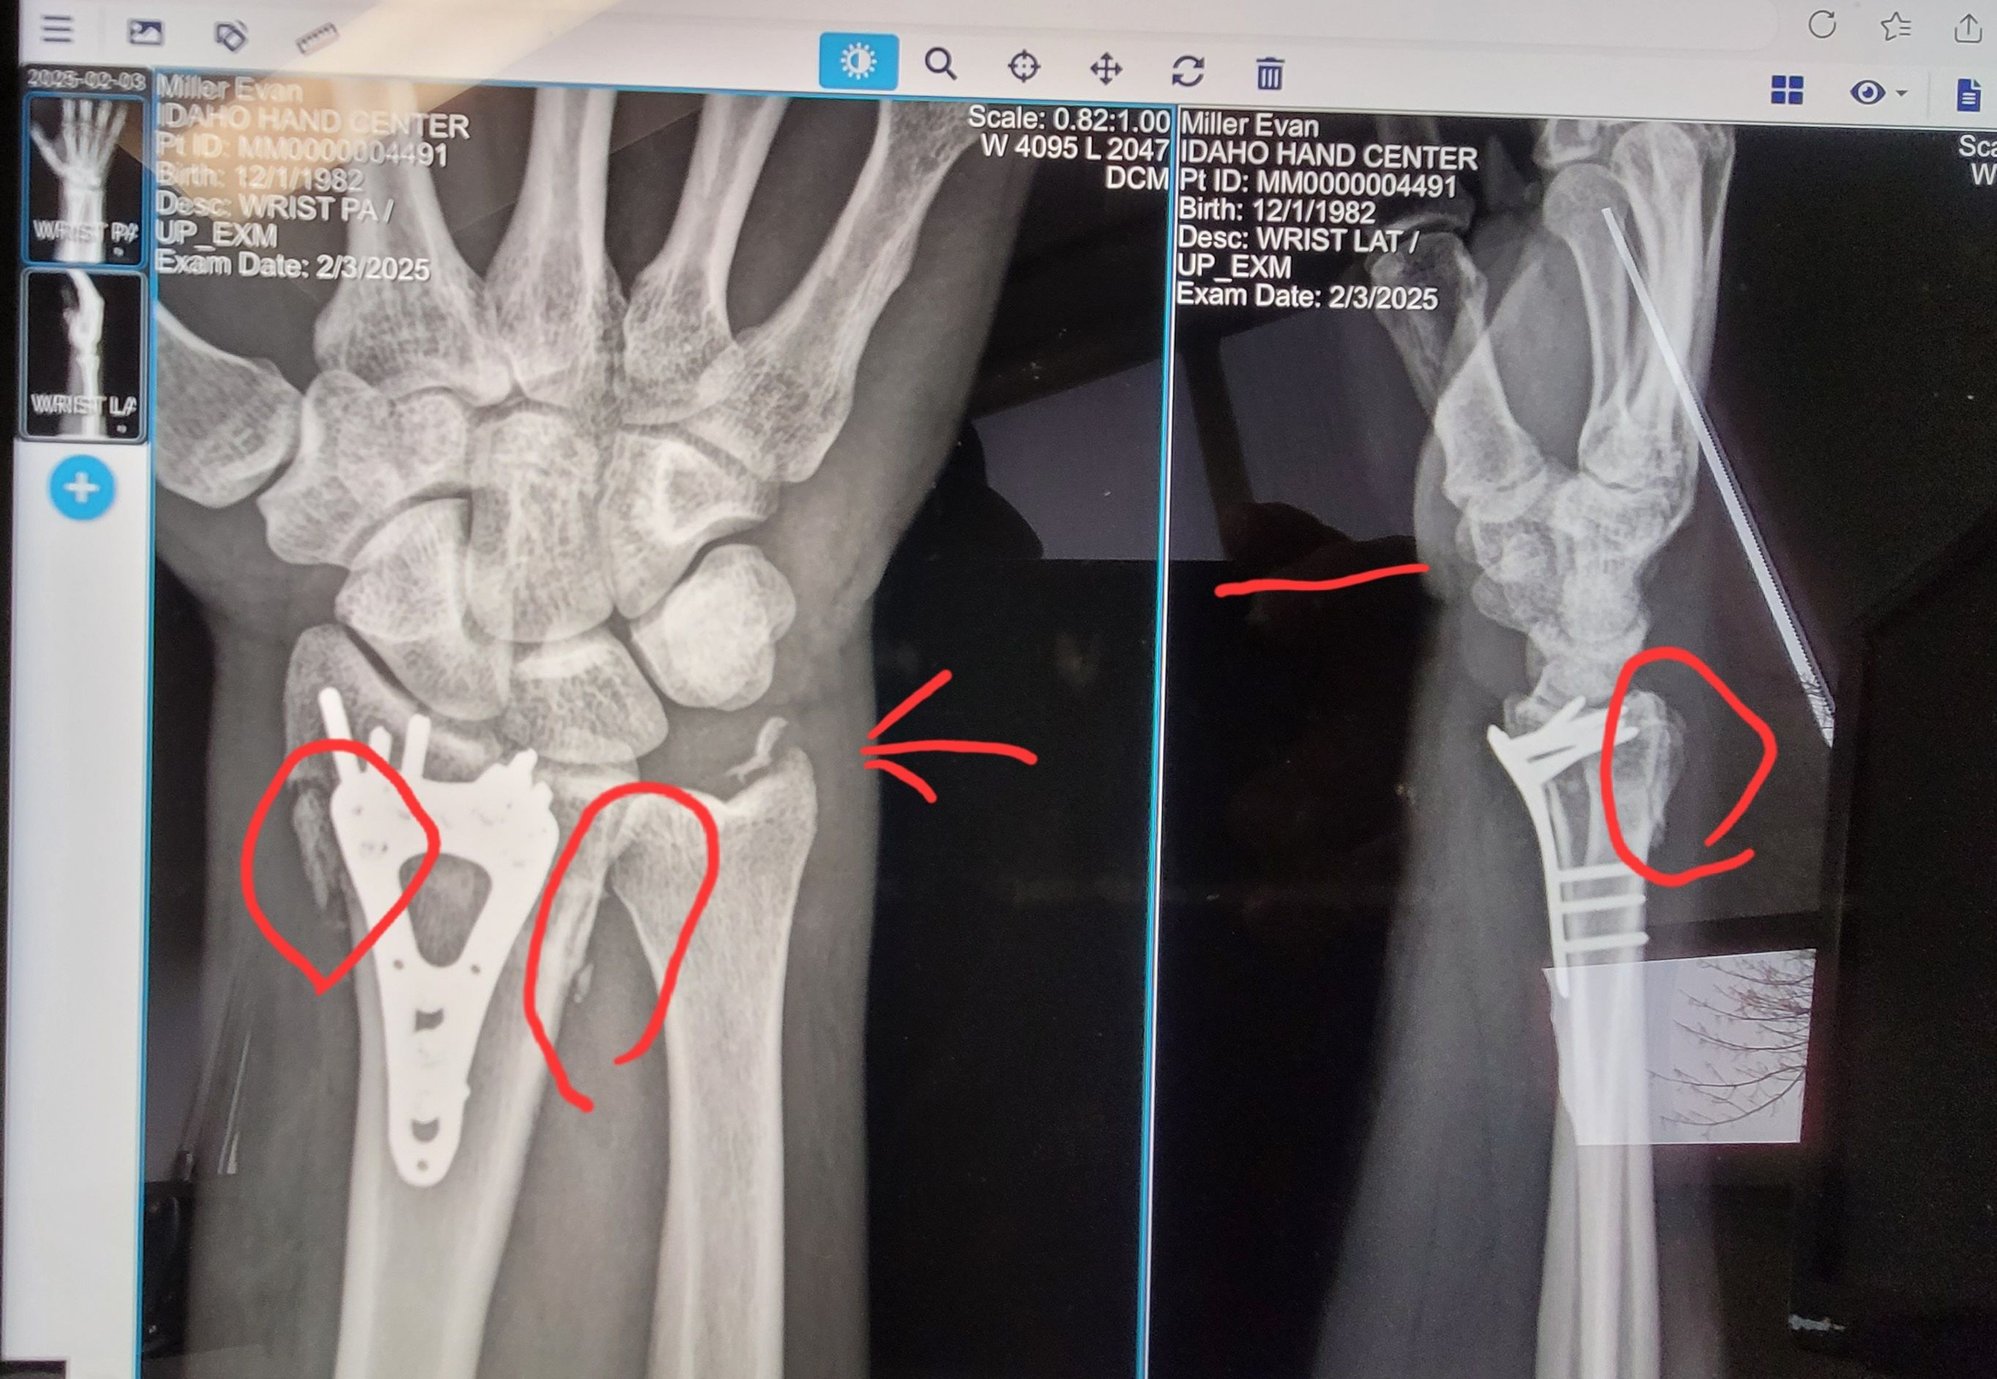

Broke my arm a couple weeks ago on sudden dirt bike stop. Even had a bone break the skin.

Went back to work almost right away